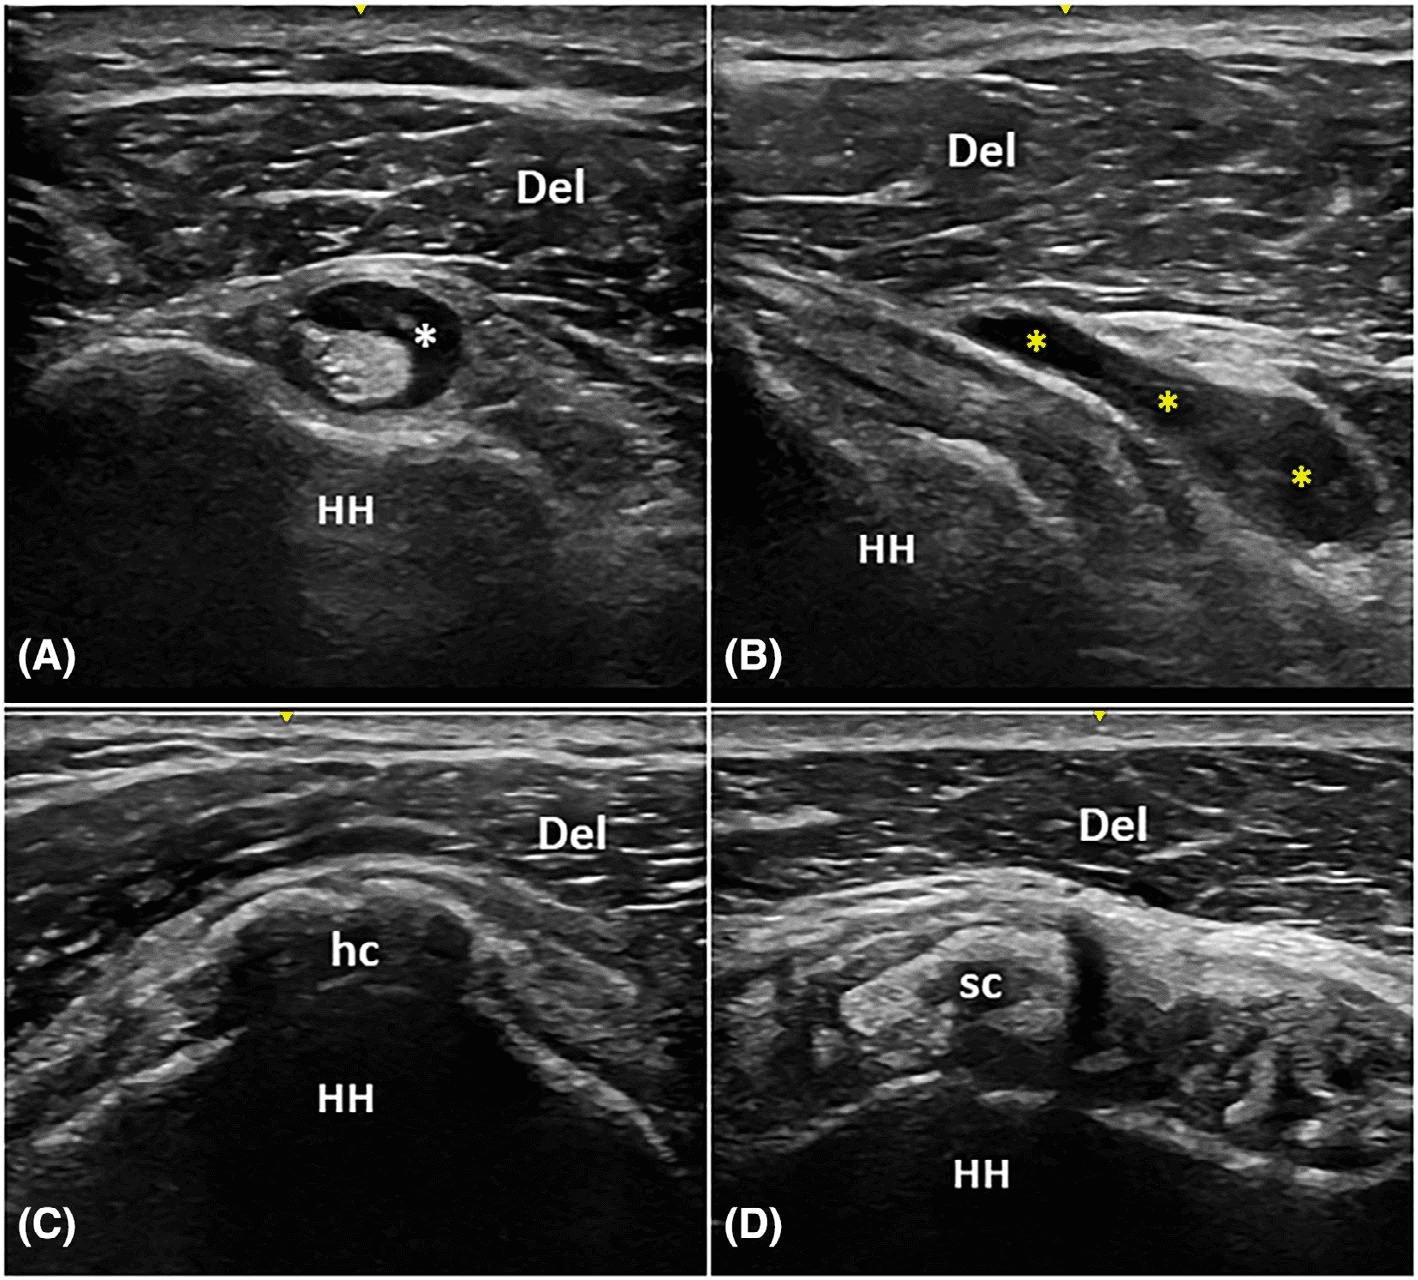

기존 연구들은 초음파상 칼슘 침착물의 형태가 치료 반응을 예측하는 지표로 활용될 수 있음을 보여왔습니다. 뚜렷한 음향 음영을 보이는 딱딱한 칼슘(Type 1)과 흐릿한 음영의 부드러운 칼슘(Type 3) 간에는 체외충격파에 대한 반응 차이가 있을 것으로 추정되어 왔습니다.

모든 환자는 치료 전 초음파 검사를 통해 관절강 내 삼출액(glenohumeral joint effusion), 견봉하-삼각근하 활액낭염(subacromial-subdeltoid bursitis), 힘줄 내 칼슘 침착물의 형태를 평가받았습니다.

건초염 논문 Figure 2 — 임상 데이터 시각화 Figure 2. Figure 2